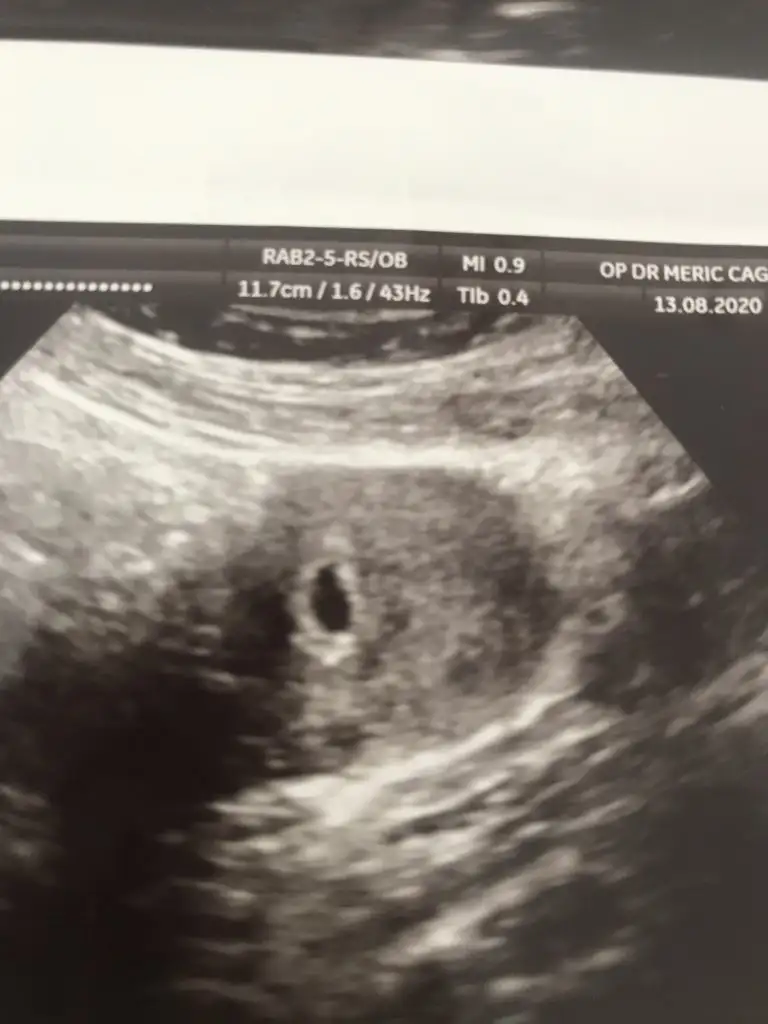

Kızlar bende doktordan geldim şimdi çok şükür keseyi gördük biraz zorlandık çünkü doktor rahmin sola dönmüş dedi böyle bir bilginiz var mı ya ilişkiye kesinlikle girmeyin dedi bir hafta sonra tekrar kontrol edecek zaten tüp bebek olduğu için 2 aydır yasak 🤣🤣🤣

Ultrasonumda böyle kızlar içini dolu gibi görüyorum dedi doktor tabi ama ben birşey göremiyorum ☺️

Bende görmedim ama kendisi yakınlaştırıO baktı içi boş değil haftaya daha net görünür dedi